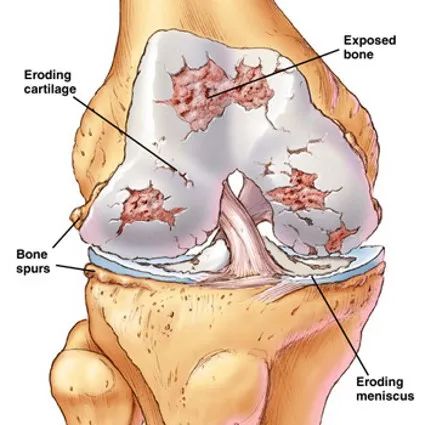

病理滑膜的各种炎性反应、增生和表面渗出。关节囊的增厚和粘连。关节软骨的软化、撕裂、磨损。骨赘形成。

X线检查基本特征1.关节间隙变窄:成人膝关节间隙为4mm,小于3mm即为关节间隙狭窄,60岁以上的老人膝关节间隙为3mm,小于2mm为关节间隙狭窄。2.软骨下骨板硬化:软骨下骨板致密、硬化,负重软骨下骨质内可见囊性改变。3.骨赘形成

关节软骨的改变:软骨水肿、软骨囊性变、软骨变薄、磨损、软骨破坏

骨质疏松症是骨总量的减少,骨骼结构松散如“蜂窝煤”一般,表现为骨脆性增加,易发骨折且不易愈合。骨关节病则是由于关节经过几十年的使用,表面的软骨发生退变、磨损、剥落,引起关节周围以及软骨下骨发生增生、硬化、骨赘形成、囊性改变。骨关节病和骨质疏松症是骨的两种不同的疾病状态,两者可以同时存在。